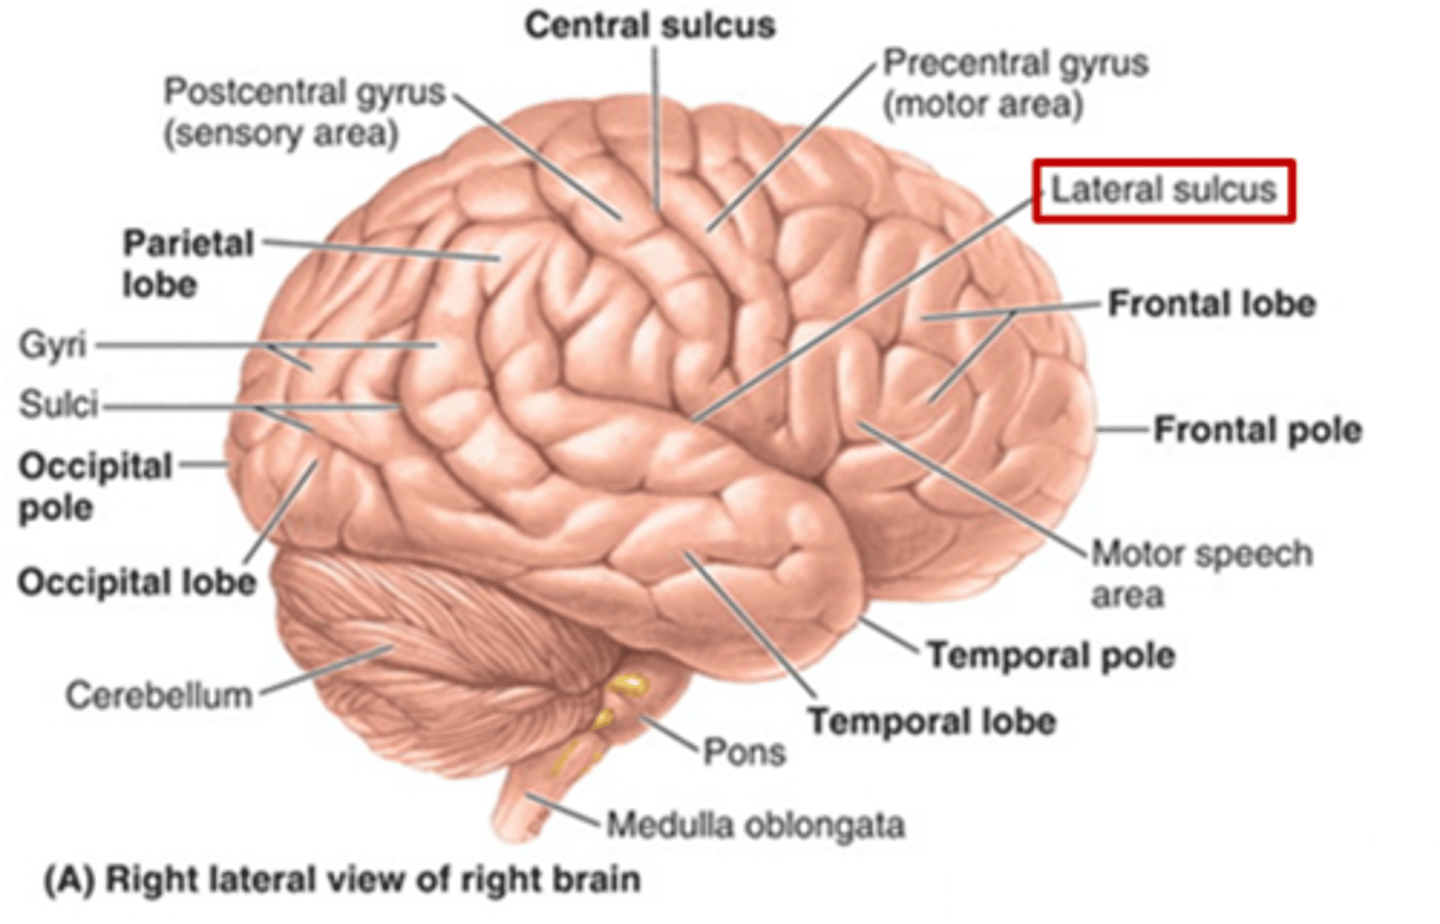

which sulcus separates the cerebral hemispheres?

longitudinal fissure

which sulcus divides the frontal lobe from the parietal lobe and divides the precentral and postcentral gyrus?

central sulcus

which sulcus divides the parietal lobe from the temporal lobe?

lateral (sylvian) sulcus/fissure

which sulcus separates the parietal lobe from the occipital lobe?

parieto-occipital sulcus

which gyrus is the primary motor complex?

precentral gyrus

which gyrus is the primary somatosensory complex?

postcentral gyrus